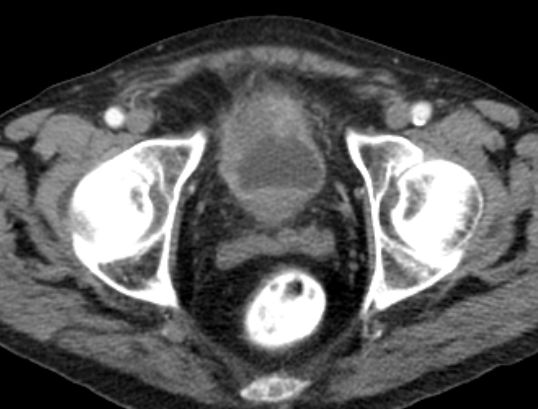

| Becken-Rezidiv | 54-jährige Frau nach radikaler Zystektomie und Anlage eines Ileumconduits wegen eines Plattenepithelkarzinoms der Harnblase vor 8 Monaten. Jetzt Verdacht eines Abszesses an der linken Beckenwand. Anlage eines Transversostomas und Drainage, später transvaginale Drainageeinlage. Jetzt Tumorfreilegung, Nekroseausräumung, Drainage. Histologie: Plattenepithelkarzinom. Destruktion des Beckenknochens links mit Einbruch ins Acetabulums. | ||

![]() |